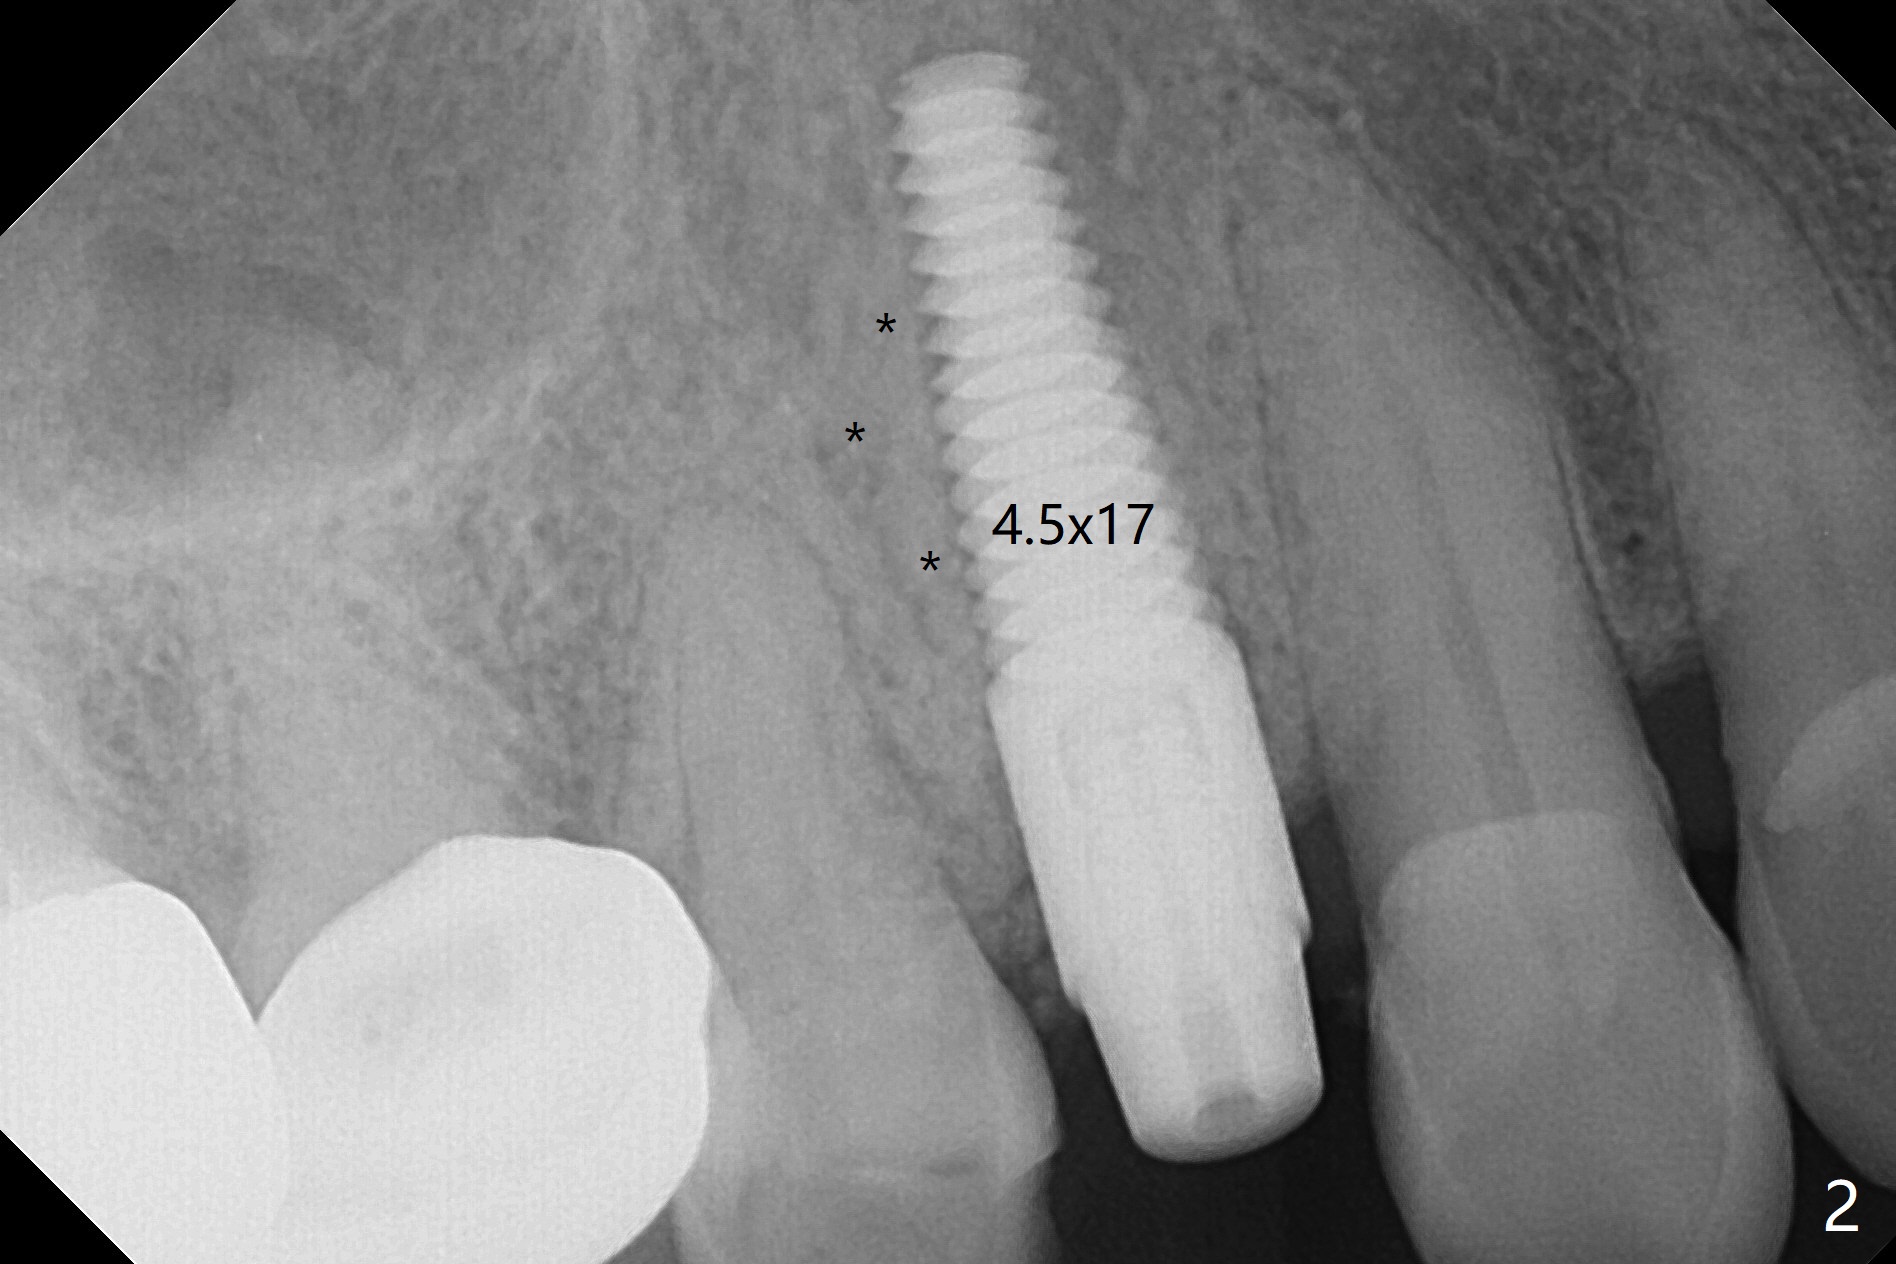

After extraction of the tooth #4 with fistula (Fig.1), the buccal bony defect is superior to the fistula. Before placement of a 4.5x17 mm tissue-level implant (Fig.2) and after osteotomy for bone-level one, PRF and mixture of autogenous bone and allograft are pushed from the socket through the buccal defect for repair (Fig.3 arrowheads). The trajectory of the implant (Fig.4) is consistent with design (Fig.5). The fistula reduces in size and in redness, while the apical elevation (as related to the underlying bone graft) remains prominent 13 days postop (Fig.6,7 *). The distal defect has been apparently repaired 9 months postop (Fig.8 *, as compared to immediately post bone graft in Fig.2). The distal defect has been apparently repaired 9 months postop (Fig.8 *, as compared to immediately post bone graft in Fig.2). The fistula disappears (Fig.9).